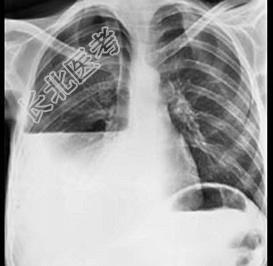

- 单项选择题如图,脓胸病人的X胸片出现液气平面, 可能有下列哪些原因 ( )

A、曾经作过胸腔穿刺

B、支气管或气管瘘

C、食管穿孔

D、膈疝合并肠穿孔

E、以上都是